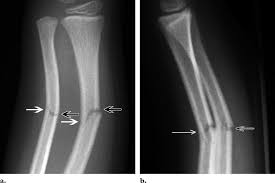

Spiral

fracture caused by twisting motion (IN NAME!!)

twisting/corkscrew pattern around bone